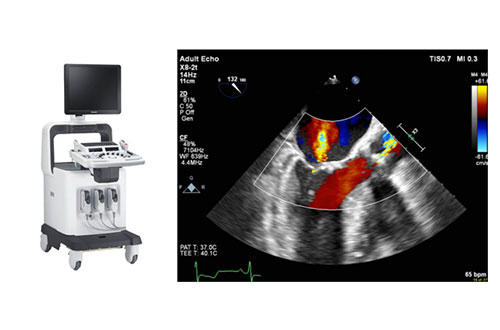

내 마음의 건강을 보는 정밀 영상 검사 심장 초음파

초음파를 이용해 심장의 판막, 심근, 혈류 등을 비침습적으로 실시간 영상으로 관찰하는 검사입니다.

방사선 노출 없이 안전하며, 심장 기능 전반을 정확히 평가할 수 있습니다.